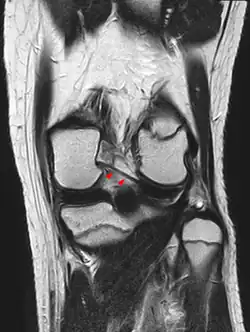

In der MRT muss der Verlauf der Ligamenta meniscofemoralia berücksichtigt werden, um eine Verwechslung mit einem verlagerten Anteil des Außenmeniskus bei einem Riss desselben zu vermeiden.[10]